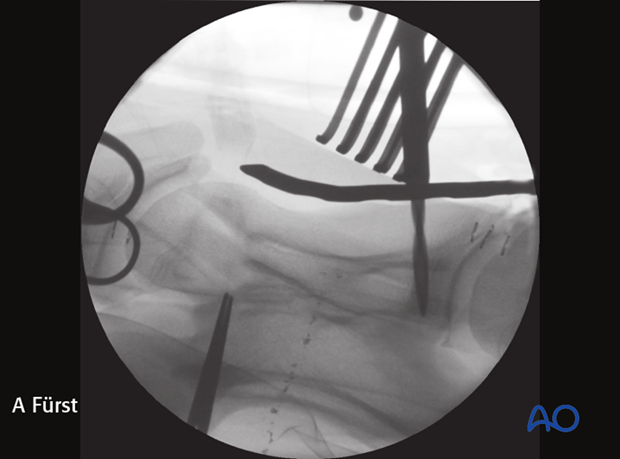

Intraoperative radiographic control of the drilling depth and screw positioning is critical to prevent penetration of the vertebral canal.

The image shows intraoperative radiographic control of the drilling depth and screw positioning.

Note: Penetration of the spinal canal with the drill must be avoided.

Intraoperative image showing penetration of the spinal canal.